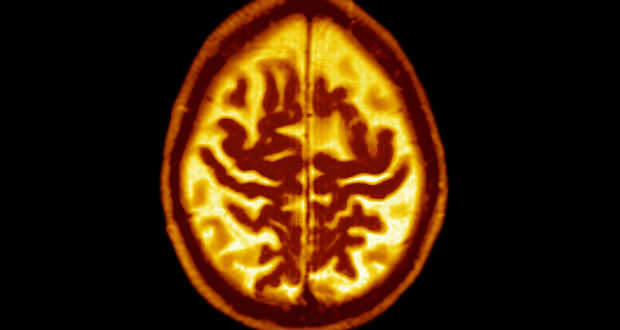

Mire félreismerhetetlen tüneteit produkálja az Alzheimer-kór, a betegek agya már súlyosan károsodott.

A neuronokat roncsoló béta-amiloid fehérje plakkokat képez az agyszövetben, és drasztikusan rontja az ember memóriát, gondolkodását, általános kognitív képességeit.